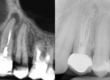

Previo al tratamiento se realiza exploración radiológica con radiografía periapical y CBCT para tener una visión tridimensional del caso. (Fig. 1) En las imágenes se ve que las raíces tienen imágenes radiolúcidas por lo que se sospecha de la existencia de conductos omitidos. Se descarta la existencia de fisuras radiculares. (Fig. 2)

Fig. 1: Estudio radiográfico previo al inicio del tratamiento, donde podemos observar en 2D y en 3D la existencia de

patología periapical.